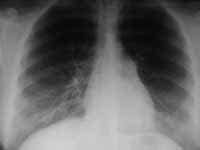

La siguiente entidad a considerar es el embolismo pulmonar. Aunque no es de ocurrencia común, la obstrucción aguda de una arteria pulmonar principal o de ramas lobares (Figura 2) o segmentarias puede dar origen al pulmón hiperlucente generalizado o focalizado, según sea el caso. Es el llamado signo de Westermark. Una gamagrafía de ventilación y de perfusión ha sido el método de imagen empleado para diferenciar entre embolismo pulmonar y enfisema.

Figura 2. TEP. Vasos pequeños en pulmón izquierdo.